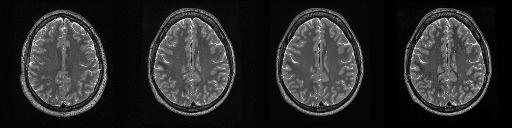

HCP T2w dataset

We utilize images from the publicly available Human Connectome Project (HCP) [51] T2-weighted (T2w) images dataset for the task of compressed sensing, which contains brain images from 47 patients. The HCP dataset includes cross-sectional images of the brain taken at different levels and angles.

Compressed sensing

We train a flow-based model from scratch on 10,000 randomly sampled images, utilizing the ncsnpp architecture [9] with minor adaptations for grayscale images. We employ compression rates , meaning . The measurement operator is given by a subsampled Fourier matrix, whose sign patterns are randomly selected. We evaluate our reconstruction algorithm’s performance on 200 randomly sampled test images.

We present the quantitative and qualitative results of compressed sensing in Tab. 1 and Fig. 4, respectively. As shown in Tab. 1, our method consistently achieves the best performance across varying compression rates . In Fig. 4, our method produces reconstructions that are more faithful to the original images, with fewer artifacts, leading to higher accuracy and clearer details.